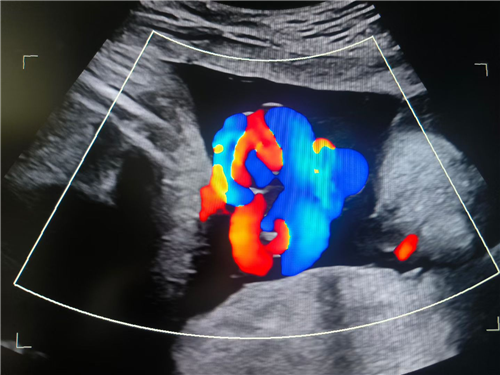

近日,一名既往有脊柱手术史的孕35周孕妇就诊妇产科门诊,因产检胎监突现异常信号,常驻我院的上海国际和平妇幼保健院黄鼎副院长带领妇产科团队迅速会诊,B超室主任联合上海专家确诊“脐带真结”,并已导致胎儿胎心下降。医院立即启动顶级应急响应,麻醉科、妇产科、新生儿科等团队采用全麻下紧急剖宫产方案,3小时完成从诊断到分娩的生命接力。

我院即将启动麻醉疼痛门诊,将为手术患者提供术前评估服务,进一步优化手术流程,提升手术安全性,为患者提供更全面的医疗保障。我院超声科在依托“上海常驻专家+本土优秀团队”的双优模式,在核心诊疗领域形成显著竞争力,尤其在产前筛查方面,凭借专业实力为母婴健康保驾护航。